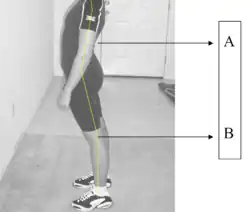

Measurement and diagnosis of lumbar hyperlordosis can be difficult. Obliteration of vertebral end-plate landmarks by interbody fusion may make the traditional measurement of segmental lumbar lordosis more difficult. Because the L4–L5 and L5–S1 levels are most commonly involved in fusion procedures or arthrodesis and contribute to normal lumbar lordosis, it is helpful to identify a reproducible and accurate means of measuring segmental lordosis at these levels.[16][17] A visible sign of hyperlordosis is an abnormally large arch of the lower back and the person appears to be puffing out their stomach and buttocks.

Lumbar hyperlordosis (also known as anterior pelvic tilt) has a noticeable impact on the height of individuals with this medical issue, a height loss of 0.5–2.5 inches (1.27–6.35 centimeters) is common.[12]

Merely slouching doesn't cause height loss, even though it may make a person look shorter, slouching may lead to perceived height loss, whereas lumbar hyperlordosis leads to actual and measured height loss. To make it easier to understand the difference, people losing a vertebra (which is around 2 inches or 5 centimeters in height) in the spine will be shorter regardless of posture. Lumbar hyperlordosis, of course, doesn't make you lose a vertebra but it bends them in such a way that your spine's vertical height is reduced.